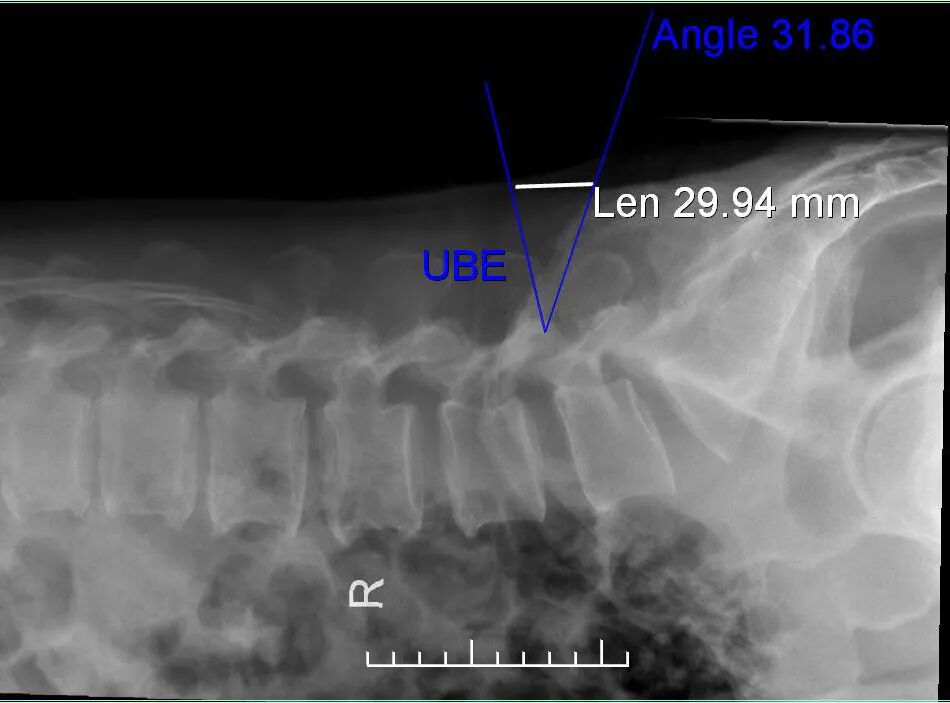

图4:术前定位影像

图5:术前定位影像

麻醉成功后,病人取俯卧位,透视下定位L4/5间隙并于左侧棘突中线旁标记皮肤切口,左侧旁开脊柱中线1cm以椎间隙水平线为中心线间隔3cm做两处纵行手术切口,远端切口钝性剥离作为工作通道,依次逐级插入扩张导杆对软组织进行扩张,近端切口扩张后放置内镜,内镜通道与工作通道汇合于左侧L4椎板与棘突交汇处,清理L4下椎板及L5. 上椎板软组织,磨钻磨除左侧L4部分下椎板,刮匙刮除L5. 上椎板止点,整块切除黄韧带,切除左侧L5部分上椎板,显露L4/5椎间隙及L5椎体后上部,切除椎间隙髓核,将L5神经根松解并牵向内侧,见脱垂髓核位于神经根肩前及腋下,将脱垂游离取出,镜下观察无活动性出血、神经根松弛,行后纵韧带及纤维环热凝成形。退出内镜及工作通道,缝合包扎切口。